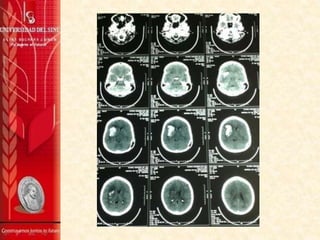

TAC DE CRÁNEO SIN CONTRASTE 27/2/2014

Se aprecia gran hematoma intraparenquimatoso

comprometiendo la región ganglio basal derecha, parte del

lóbulo frontal y temporal del mismo lado, sus contornos son

irregulares y sus diámetros máximos del plano axial son de 59

mm (AP) x 27 mm (TRV). Sus características están a favor de

una etiología hipertensiva entre otros diagnósticos

diferenciales.

La línea media está desviada hacia la izquierda

aproximadamente 6 mm por el efecto de masa producido por

el hematoma, y colapsa casi totalmente el ventrículo lateral

derecho.

No se aprecian alteraciones en la fosa posterior.

IMPRESIÓN:

1. Hematoma intraparenquimatoso comprometiendo la

región ganglio-basal derecha, parte del lóbulo frontal y

temporal del mismo, muy probablemente de origen

hipertensivo.